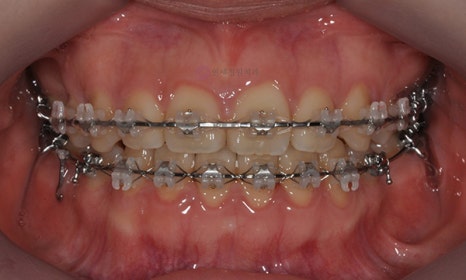

오른쪽 아래 작은 어금니에 버튼을 붙여 고무줄을 걸어 제위치로 끌어당기고 있는 모습입니다.

2021.5